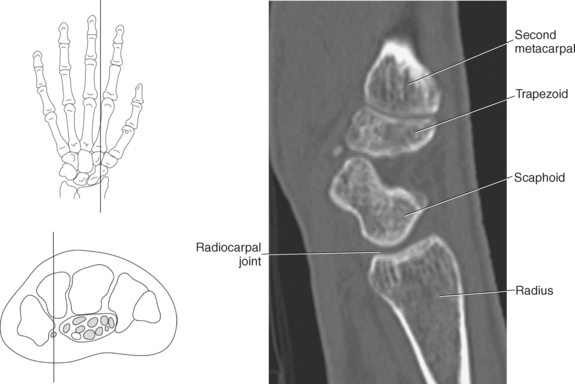

The bony anatomy of the wrist and hand consists of the distal radius and ulna, 8 carpal bones, 5 metacarpals, and 14 phalanges (Figure 9.101). Both the distal radius and ulna have a conical styloid process that acts as an attachment site for ligaments. The radial styloid process is located on the lateral surface of the radius, whereas the ulnar styloid process is located on the posteromedial side of the ulna. The carpal bones are arranged in proximal and distal rows. Located in the proximal row of carpal bones are the scaphoid (navicular), lunate (semilunar), triquetral (triquetrum), and pisiform bones. The pisiform is considered a sesamoid bone that is embedded in the tendon of the flexor carpi ulnaris. The distal row consists of the trapezium (greater multangular), trapezoid (lesser multangular), capitate (os magnum), and hamate (unciform) bones (Figures 9.102 through 9.114). The five metacarpals are small tubular bones with a proximal end (base), distal end (head), and shaft (body). The 14 phalanges that make up the fingers are short tubular bones. Like the metacarpals, each phalanx consists of a proximal (base), middle (body or diaphysis), and distal (head) portion. Each digit consists of 3 phalanges (proximal, middle, and distal), except for the thumb (first digit), which has only 2 phalanges (proximal and distal). The articulation of the phalanges of the second through fifth digits creates three interphalangeal joints: the metacarpophalangeal (MCP) joints classified as condyloid joints, proximal interphalangeal (PIP), and distal interphalangeal (DIP). The proximal and distal interphalangeal joints are classified as hinge joints (Figure 9.101). The first digit, which consists of 2 phalanges, has just two joints: the MCP joint, classified as a saddle joint, and an interphalangeal joint, classified as a hinge joint (Figure 9.101).

The joints of the wrist and hand are quite complex and consist of the following: distal radioulnar articulation, radiocarpal articulation (proximal joint of hand), midcarpal articulation (distal joint of hand), intercarpal articulations (articulations between proximal and distal carpals), carpometacarpal articulations (between carpals and metacarpals), the intermetacarpal articulations (between bases of metacarpals two through five) and the interphalangeal joints (between phalanges of each digit) (Figures 9.111 and 9.115). The distal radioulnar articulation, also called the distal radioulnar joint (DRUJ), is created when the ulnar notch of the radius moves around the articular circumference of the ulna, providing the movements of supination and pronation. The main stabilizing element of the DRUJ is an articular disk called the triangular fibrocartilage complex (TFCC). The TFCC is a fan-shaped band of fibrous tissue that originates on the medial surface of the distal radius and traverses horizontally to insert on the ulnar styloid process (Figures 9.115 and 9.116). It rotates against the distal surface of the ulnar head during pronation and supination and separates the ulna from the carpal bones. The proximal surface of the radiocarpal articulation is formed by the articular carpal surface of the radius and the TFCC, whereas the distal surface is formed by the articular surfaces of the scaphoid, lunate, and triquetrum and the interosseous ligaments connecting them (Figures 9.111 through 9.115). The midcarpal joint is formed by the articulations between the proximal and distal carpal rows (Figures 9.110 and 9.115). The articulation between the carpals within each row creates the intercarpal joints (Figures 9.111 and 9.115). The carpometacarpal joints are formed by the articulations between the carpus and the five metacarpals (Figure 9.111 and 9.115). The carpometacarpal joint of the thumb is an independent joint formed by the articular surfaces of the trapezium and first metacarpal, creating a pure saddle joint. The carpometacarpal articulations of the two to five digits are amphiarthrotic joints with little mobility (Figures 9.105 and 9.115). The intermetacarpal articulation exists between the base of the metacarpals and is joined by the palmar and dorsal metacarpal ligaments (Figure 9.115).